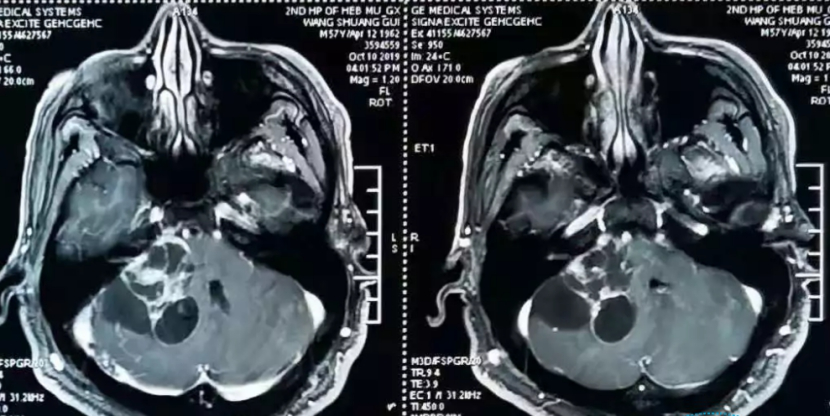

听神经瘤是一种生长在耳蜗前庭神经上的良性(非癌性)脑肿瘤。耳蜗前庭神经(也称为八脑神经)是由连接内耳和大脑的三根神经组成的。耳蜗神经是听觉信息的一个分支。另外两个分支--下前庭神经和上前庭神经--将平衡信息传递给大脑。如果听神经瘤没有得到诊断或治疗,它可能会长得足够大,压迫脑干的重要结构,造成严重的危及生命的问题。

听神经瘤的主要症状是听力丧失和耳鸣,是由肿瘤压迫听觉神经引起。由于这两大症状更多来源于耳朵本身的问题,无论是内耳、外耳、中耳,任何一个部位出现问题都可以引起耳鸣,所以患者就诊较多的还是五官科。但INC国际神经外科专家提醒,如果耳鸣症状持续,而且慢慢有听力下降的病人,还是需要高度怀疑颅内的问题。临床上确实有不少听神经瘤早期患者会难以识别,等到肿瘤长大了,出现了一些其他问题才被确诊。比如听神经瘤病程时间长了,除了听力丧失之外,还可能会影响到面神经,发生面瘫,继续发展到脑干还可能会出现脑积水。一旦出现这些问题,处理起来就会更加棘手,治疗效果远不及早期治疗。

目前国内外对于听神经瘤的治疗都是优选手术切除。听神经瘤的外科手术已经有长达120年的历史了,发展至今,手术的成功率已经的高。但若要完整切除听神经瘤的同时还要大水平保留听力、面神经功能,保障手术成功的同时还要兼顾病人后期的生活质量,这对于当前国际范围内的诸多神经外科医生来说,还是一个较大的挑战。这是由于听神经瘤位于颅底中心位置,周围重要的神经、血管众多。特别是听神经瘤长得过大,术中很难完整剥离,较易伤及与之毗邻并行的面神经、三叉神经等,手术做好了,但有较大可能引起面瘫、听力丧失等并发症。